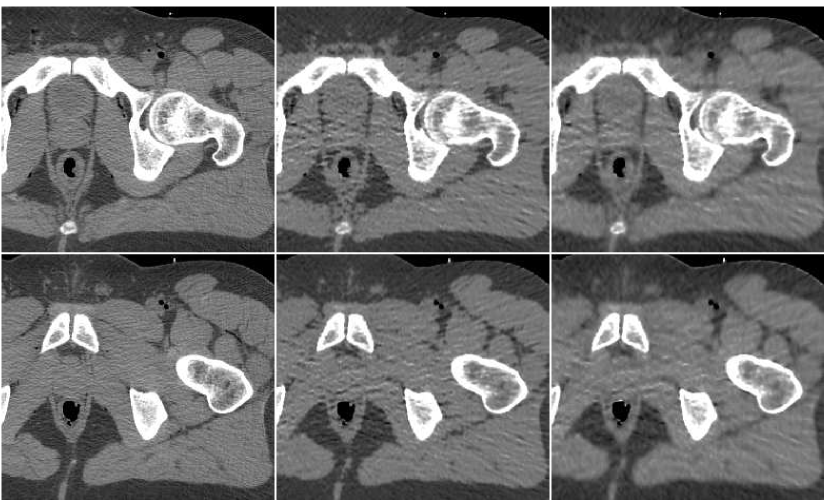

In Figure 10 we display the fusion result along with individual PWLS reconstructions, used in the fusion process. The lower part of the figure contains the absolute-valued error images. The fusion result has a higher visual quality than any of the three underlying images. Comparing to those images, the noise level in the fusion image is the lowest, and the tissue texture is closer to the original. The sharpness is the same as in the lower middle PWLS image. The SNR values (stated in the Figure) also point to the improvement in quality. The SSIM of the fusion image is , while the sequence of PWLS results have the SSIM values of (corresponding to the lower row of Figure 10, left to right). A reconstruction of an additional test image is displayed in Figure 11. The effect of the fusion observed here is similar to the one in the previous reconstruction. We conclude that the ANN-based fusion can contribute also to the iterative reconstruction, without requiring any additional iterations; the computational cost of the fusion, exercised after the reconstruction, is lower by an order of magnitude than that of the iterative process.

![]() |